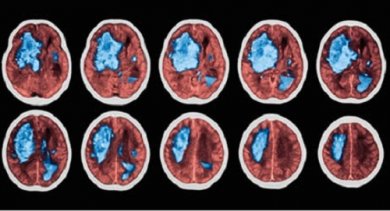

Un’emorragia cerebrale, o ictus emorragico, nella maggior parte dei casi si produce quando i vasi sanguigni che si trovano all’interno del cervello o sulla sua superficie si rompono, facendo fuoriuscire il sangue nella sostanza grigia circostante. I sintomi possono variare enormemente, a seconda della gravità del caso e dell’area del cervello colpita.